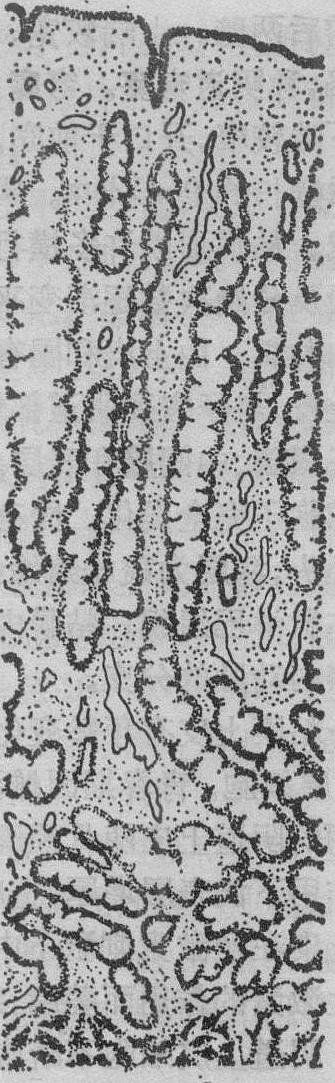

增生晚期 约在月经周期第11~14天。内膜增厚达2~3mm。腺体继续增长,弯曲度增加(图2)。腺上皮细胞的假复层现象更为明显。上皮细胞呈高柱状,微绒毛增多,核长形,常有1~2个核仁。胞质中RNA、AlP的含量增加。粗面内质网高度发育且扩张,微管和微丝发育并从细胞底部伸到高尔基复合体,线粒体增多并有分支。接近排卵时腺上皮细胞核居中央,大量线粒体、内质网位于上部,细胞基底部出现糖原颗粒。在HE染色的切片中,因糖原被溶解而呈现为核下空泡。内膜基质细胞增生,分裂相多。部分细胞呈星形,胞质少,核仁明显,分裂活跃,彼此以突起相连成网。此时功能层可分为深浅两层。浅层即近腔面的细胞富含RNA,到分泌期时将形成致密层。深层的细胞RNA含量少,将形成内膜海绵层。螺旋动脉继续增长,螺旋程度增加。管壁增厚,有弹性纤维环绕。

图2 子宫内膜增生晚期(月经周期第14天)